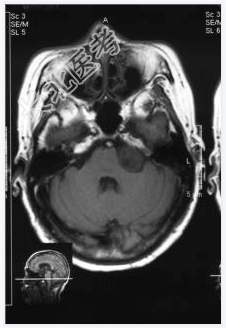

- [材料题] 患者,女性,71岁,因耳鸣、双下肢乏力4~5月,进行性发展入院。体检:左耳听力下降,行走碎步,四肢肌力Ⅴ级,肌张力略高。临床诊断:帕金森综合征。做头颅MRI检查。

- 简答题1、请问该病例诊断是什么?

- 简答题2、请问诊断依据是什么?

- 简答题3、请问鉴别诊断有哪些?

- 简答题4、左听神经鞘瘤的典型症状是什么,以及它是如何影响患者的听力和平衡功能的?

- 简答题5、左听神经鞘瘤治疗措施有哪些?